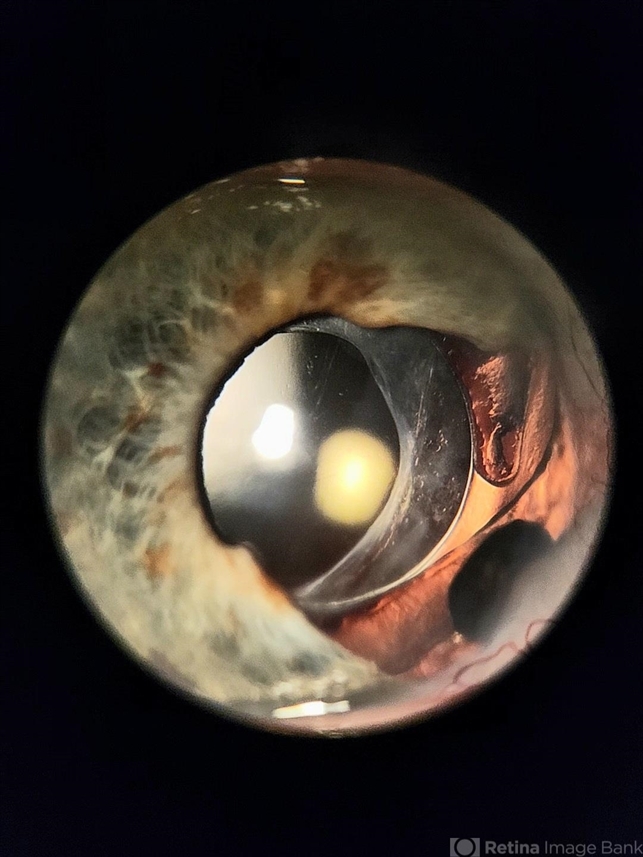

- melanoma, iris melanoma

- Virginia Gebhart, Retina Consultants of Carolina

Photo slit lamp biomicroscope

Samsung Galaxy

- 85 year old female with small pigmented lesion present s/p sectoral iridectomy in 2006. Lesion is suspicious for recurrence of melanoma after 18 years. Stable compared to previous exam in March 2024, unclear if this is a new lesion or has been present for an extended time. Will monitor closely.